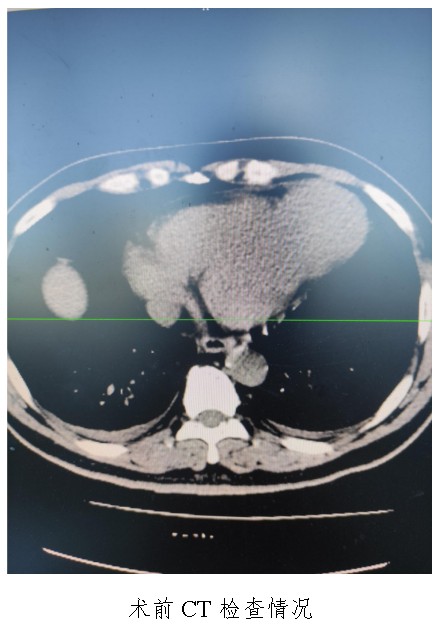

10月18日,50歲的孟先生因反復(fù)胸悶氣促一周,夜間不能平臥來衡陽市中心醫(yī)院心胸外科就診,經(jīng)心臟超聲檢查提示左心室前壁中下段及心尖部巨大室壁瘤,66×57mm,最薄處約3mm?;颊哂卸嗄晏悄虿〔∈?,既往有無癥狀心肌梗死病史,曾行PCI治療。入科后,廖金文主任、屈云劍副主任組織心內(nèi)、麻醉、體外循環(huán)、重癥醫(yī)學(xué)科對(duì)病人病情進(jìn)行了多學(xué)科討論,一致認(rèn)為手術(shù)是治療該病例的唯一手段。經(jīng)過充分的術(shù)前準(zhǔn)備,10月24日,心臟外科團(tuán)隊(duì)給患者實(shí)施了左心室室壁瘤切除加左心室修補(bǔ)成型手術(shù),手術(shù)順利,術(shù)后經(jīng)過精心的治療管理,患者恢復(fù)良好,康復(fù)出院。該病例的手術(shù)成功,不僅是術(shù)中及手術(shù)團(tuán)隊(duì)智慧的結(jié)晶,也是多學(xué)科合作的結(jié)果,展示了衡陽市中心醫(yī)院處理復(fù)雜危重患者的能力。